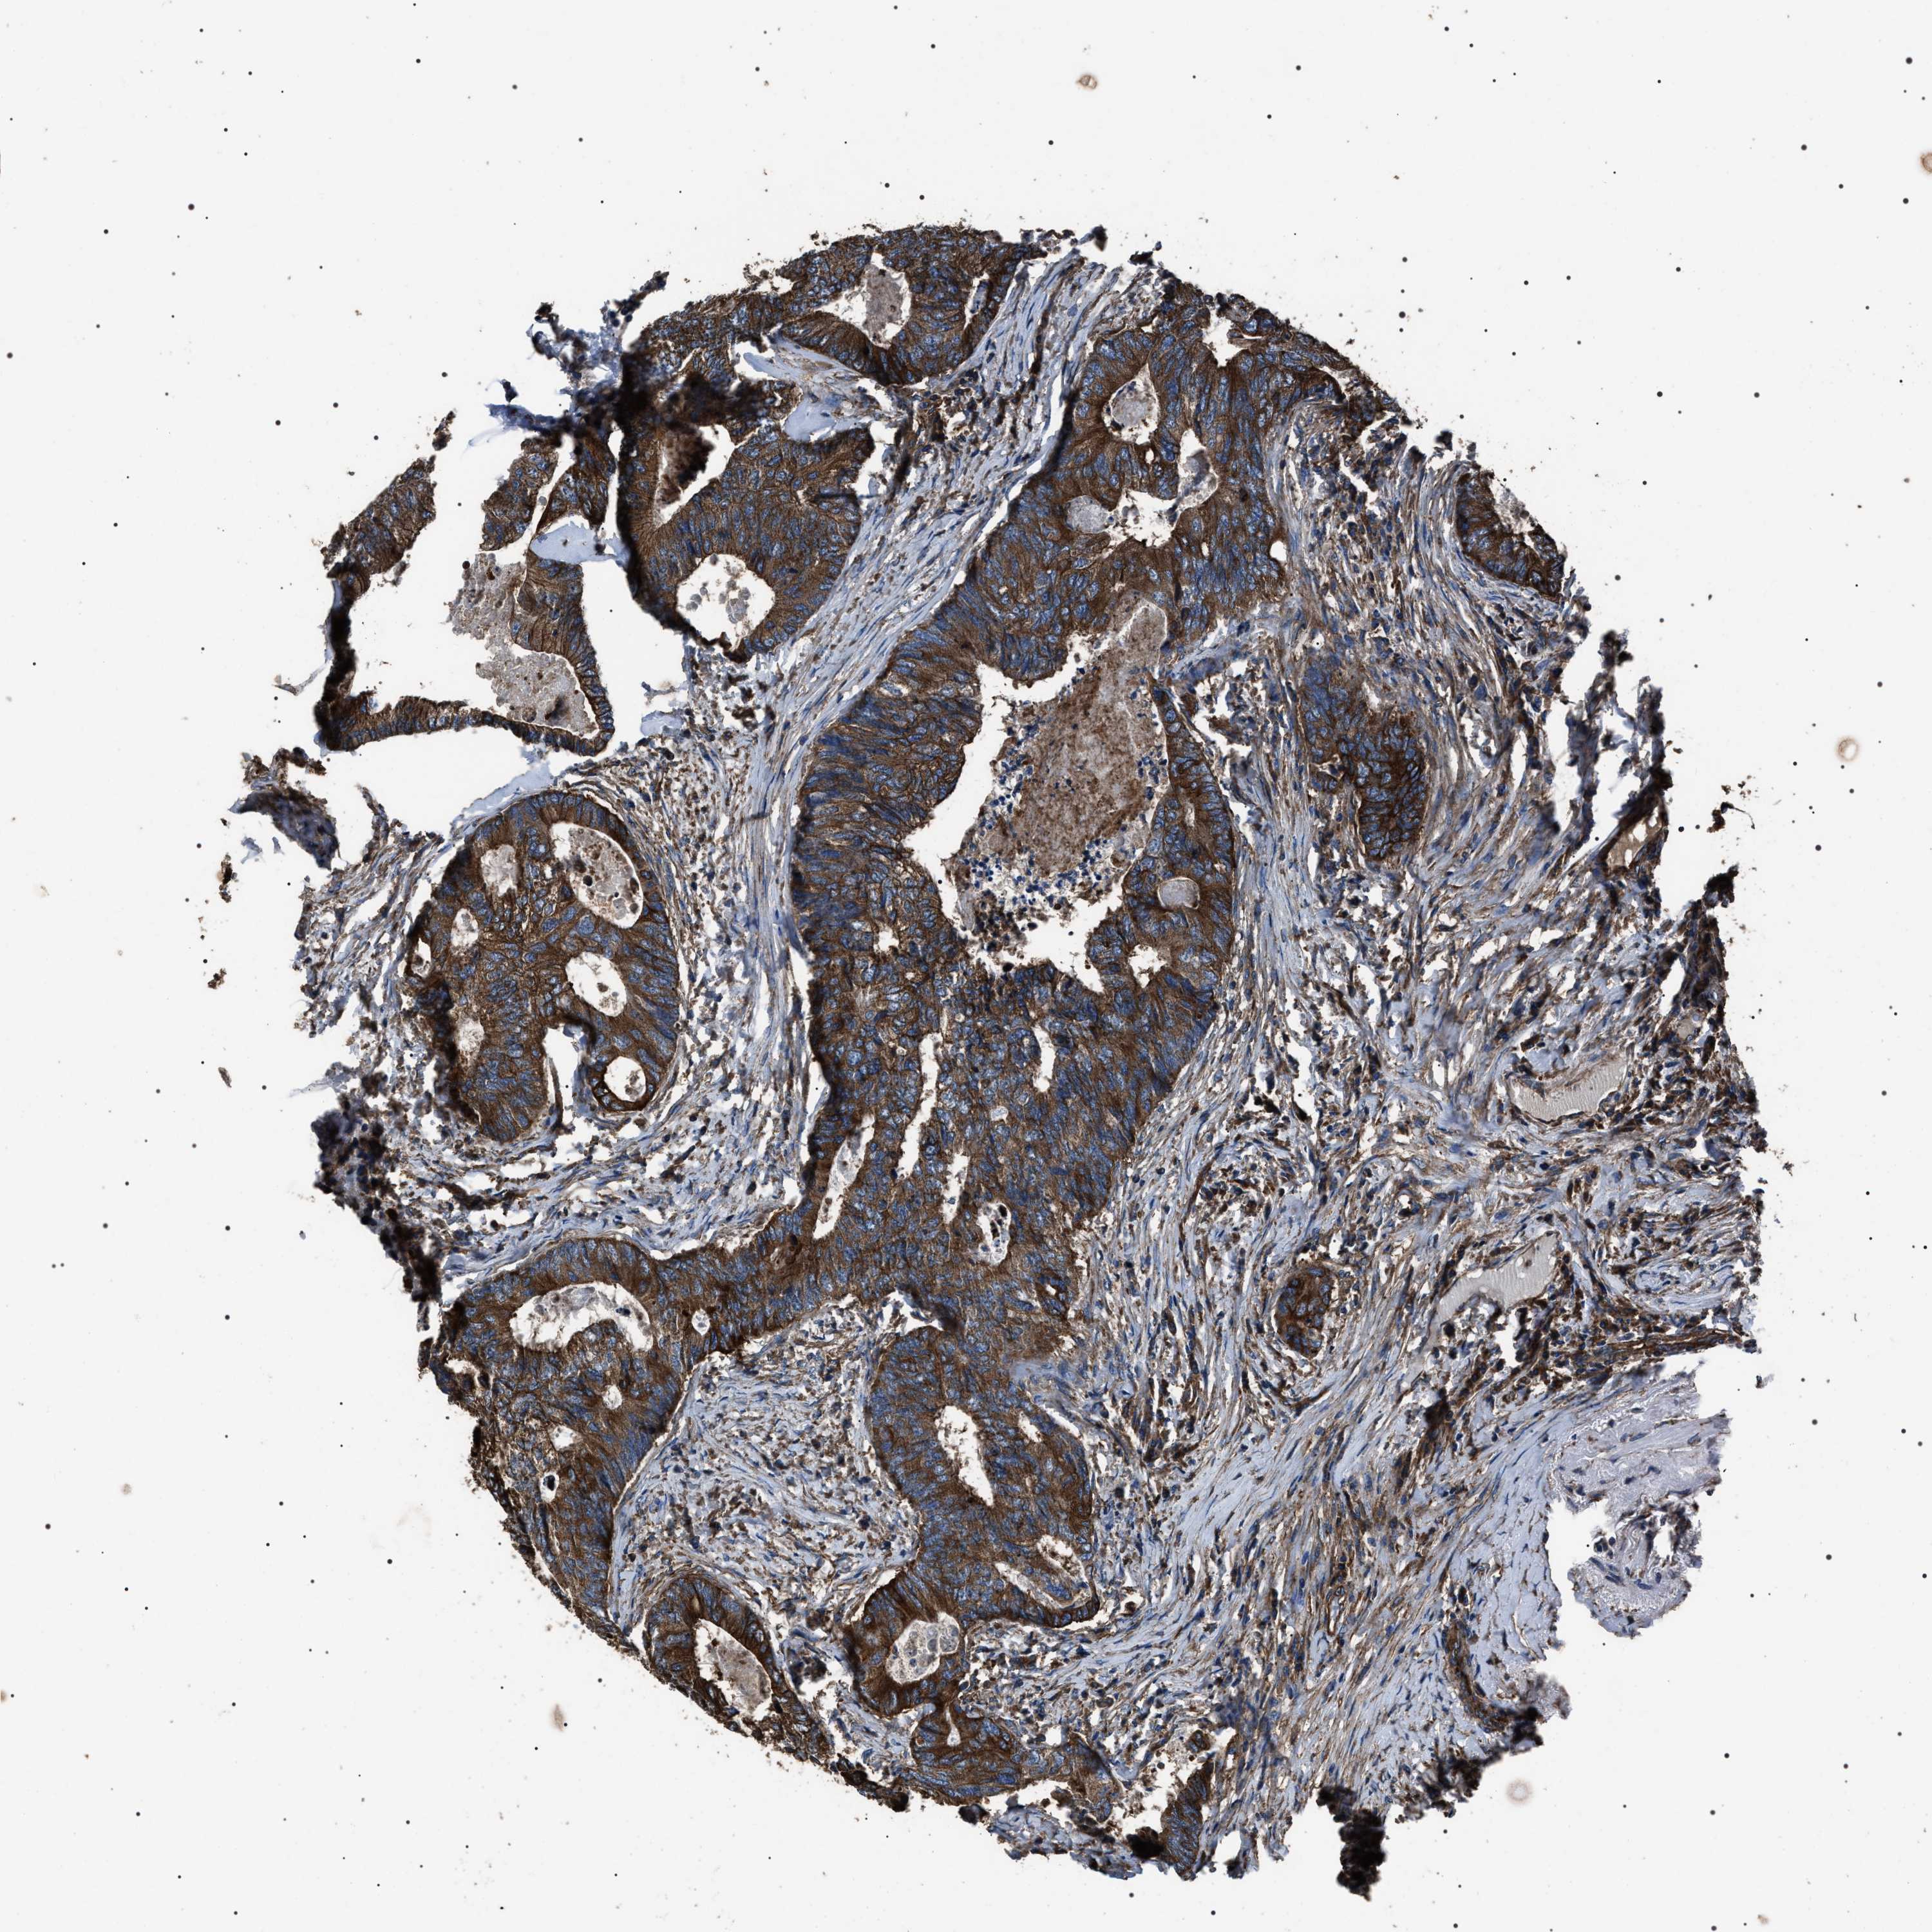

CANCER COLORECTAL CANCER Show tissue menu

Colorectal cancer

Human cancer

Rectum adenocarcinoma